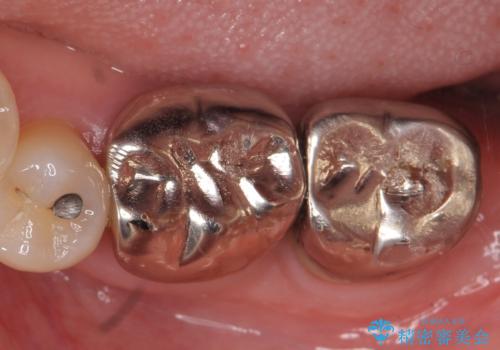

- 左下の奥歯が激しく痛むので診て欲しいといらっしゃった方の症例です。

左下7番目の歯に根尖病変を認めたため、再根管治療を行いました。

症状の消失を確認後、オールセラミッククラウンによる補綴を行いました。